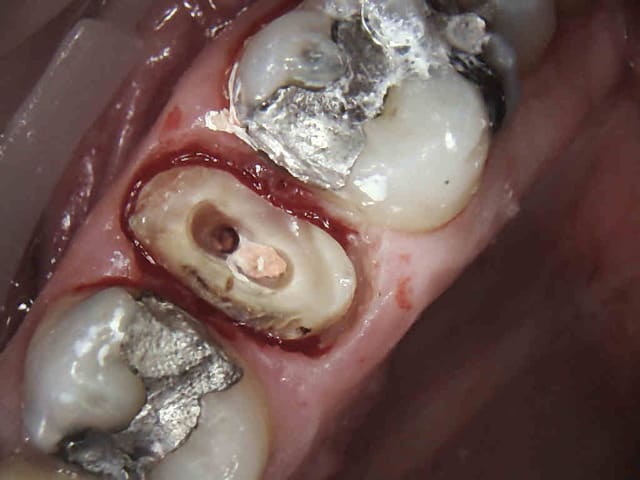

Souvent il n'y a rien, c'est plus facile. On peut d'ailleurs illustrer en quasi direct ses propos tellement c'est fréquent. Cas tous frais.-)))))

1 bd9s5w - Eugenol

2 c9r7kc - Eugenol

3 wheqza - Eugenol

4 ass1cx - Eugenol